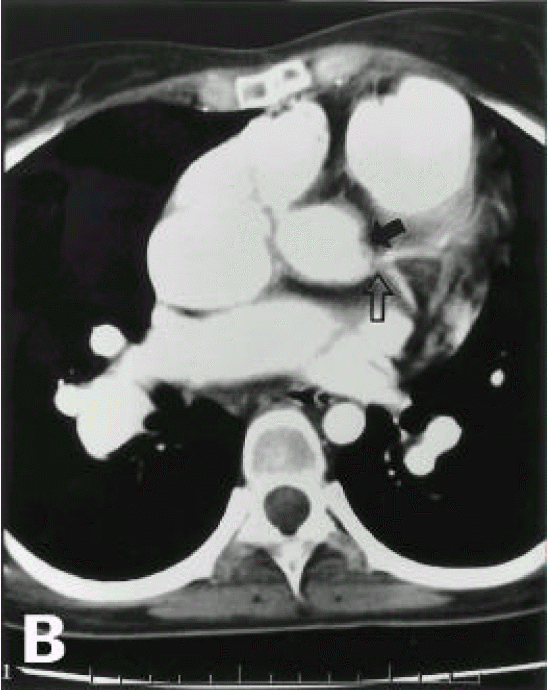

A diagnosis of Eisenmenger syndrome was made. The base-line study for heart-lung transplantation, including chest computed tomography (CT), cardiac catheterization and coronary angiography were undertaken. Chest CT scan with contrast revealed markedly dilated pulmonary trunk and both pulmonary arteries (Figure 2A), a concave disfigurement of the left side of the ascending aorta and nearly total occlusion the ostium of the left main coronary artery that was retrogradly filled with collateral circulation from the right coronary artery (Figure 2B). That was suggestive of compression of the left side of the aorta and the left main coronary artery together by the pulmonary trunk passing by the ascending aorta’s left side. Cardiac catheterization revealed PASP of 105 mmHg, Qp/Qs of 1 and Rp/Rs of 1.4 (Figure 3), which mean no remaining shunt but much aggravated pulmonary hypertension compatible with Eisenmenger syndrome compared with preoperative data. The coronary angiography showed normal right coronary artery and the collaterals that came out from the conus branch to mid-left anterior descending artery (LAD) and that from the distal right coronary artery to the left circumflex artery (LCX) and to the distal LAD, respectively (Figure 4, 5). Engagement of the left main coronary artery with the diagnostic coronary catheter was not available. On aortography, the left main coronary artery was not visualized with no stump, suggesting total occlusion of the ostium of the left main coronary artery (Figure 6). There was no other luminal lesion in the remaining part of the coronary artery system and the thoracic as well as the abdominal aorta.

Figure 2A, 2B.Figure 2A, 2B.

Chest CT scan with contrast. Markedly dilated pulmonary trunk and pulmonary arteries (Figure 2A). There are a concave disfigurement of the left side of the ascending aorta (closed arrow) and just beside, the focally occluded left main coronary artery (open arrow) that was retrogradly contrasted by collateral circulation from the right coronary artery (Figure 2B)

In our case, pulmonary hypertension due to ASD had already been present before the corrective surgery and it was progressively aggravated without improvement after the correction of the shunt up to the current admission. Therefore, the left main coronary artery had been continuously compressed, in spite of the post-closure status for ASD. We could rule out the other possible reasons for the negative results of the serologic tests for syphilis, other rheumatoid diseases and the absence of other manifestations of systemic vasculitis. The reason for disfigurement of the left side ascending aorta and the ostium of the left main coronary artery was considered to be an extrinsic compression owing to extremely dilated pulmonary artery (Figure 2B).

Figure 2A, 2B.